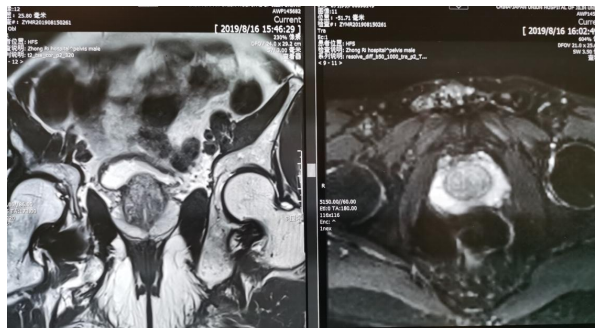

前列腺增生

膀胱癌